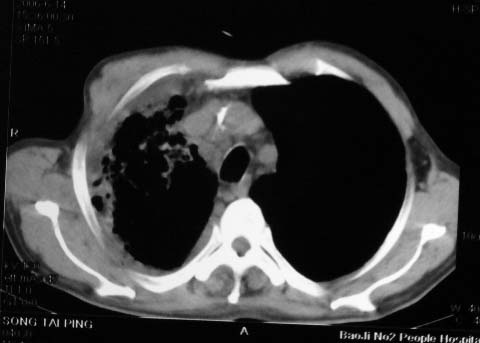

影象表现:右肺上叶大片状、网格状及索条致密影,蜂窝影,其内参杂斑点状小结节,密度不均匀,内见含气支气管像,纵隔内见肿大淋巴结.

抗感染病变无明显改善,右上叶大片状增弥不均匀病灶,夹杂网状及支气管充气像,肺门纵隔淋巴结肿大,右侧胸腔积液。考虑1混合感染伴肺间质改变[警惕特殊感染,如真菌]。2细支气管肺泡癌。建议结合临床及进一步检查[如痰,胸水脱落细胞检查及支气管镜检灌洗或穿刺活检

影象表现:右肺上叶大片状、网格状及索条致密影,蜂窝影,其内参杂斑点状小结节,密度不均匀,内见枯枝样含气支气管像,纵隔内见肿大淋巴结.胸膜广泛增厚,前胸壁似受累.少量胸腔积液.纵隔内淋巴结的直径>1.5cm.右侧胸廓体积缩小.考虑:1 肺结核合并间质纤维化 2 细支气管肺泡癌

右肺上叶大片状、网格状及索条致密影,蜂窝影,其内参杂斑点状小结节,密度不均匀,内见枯枝样含气支气管像,纵隔内见肿大淋巴结.胸膜广泛增厚,前胸壁受累增厚.少量胸腔积液.纵隔内淋巴结的直径>1.5cm.右侧胸廓体积缩小.考虑: 细支气管肺泡癌并肺内癌性淋巴管炎。